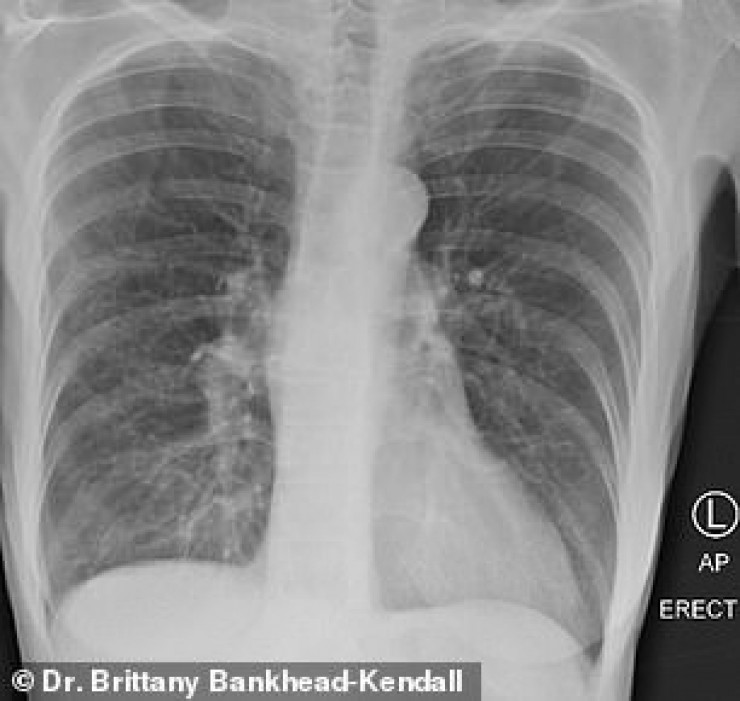

Доцент Центра медицинских наук Техасского технологического университета, доктор Бриттани Бэнкхед-Кендалл показала три рентгеновских снимка легких: здорового человека, курильщика и пациента с коронавирусом.

У курильщика они частично побелели от рубцов, и снимок выглядит слегка туманным.